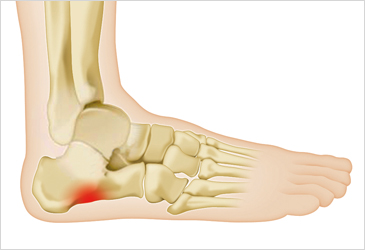

발바닥통증의 원인 고통성 족부 변형 (뼈 돌출 등)

- 발바닥의 뼈나 관절의 이상으로 인해 통증이 발생할 수 있습니다. 뼈의 돌출이나 과도한 뼈 성장(예: 발가락의 뼈가 튀어나오는 경우) 등이 그 예입니다. 이 경우 신발이 맞지 않거나 발에 가해지는 압력이 증가하여 통증이 유발됩니다.